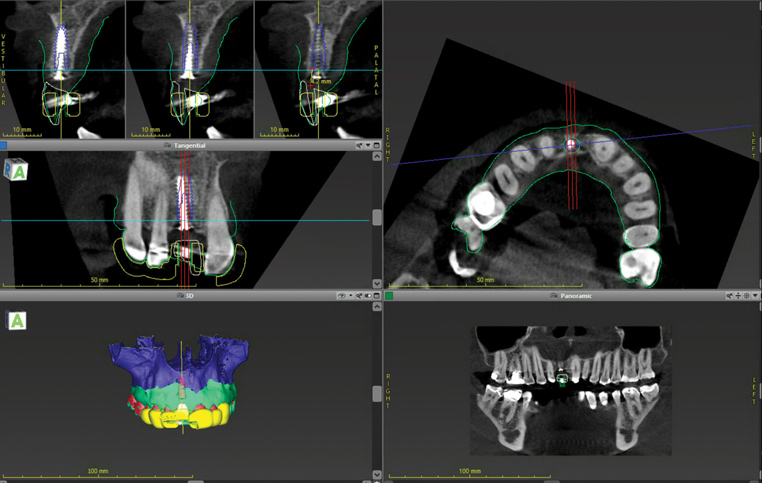

When the patient returned 4 months after the initial procedure for reevaluation, she underwent supportive periodontal therapy and was provided with detailed oral hygiene instructions (Figure 13). An intraoral scan and a postoperative CBCT scan were taken to evaluate both the horizontal and vertical hard- and soft-tissue gain. Next, implant planning software was used to merge the STL and DICOM data, which facilitated the creation of a digital wax-up (Figure 14).

The digital wax up allowed the implant position to be planned based on the ideal prosthetic position of the final restoration (Figure 14). The planned implant position adhered to the aforementioned guidelines for ideal implant placement regarding the buccal, interproximal, and apical bone, and its platform would be located 4-mm apical to the planned restorative margin. In the coronal plane, the implant was centered with the gingival zenith in a position that was located approximately 1-mm distal to the midline of the edentulous space. Following implant planning, a tooth-supported surgical guide was designed and then 3D-printed to facilitate fully guided surgical implant placement.

(14.) Three-dimensional implant treatment planning.

Figure 14